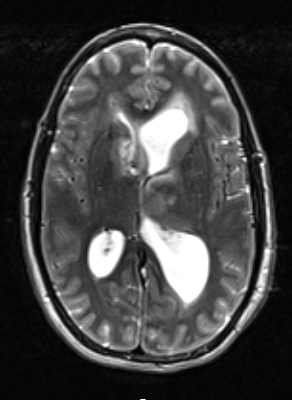

2A3 HGAP (Case 2) T2W - Copy

A T2-weighted scan with contrast shows a hyperintense mass.